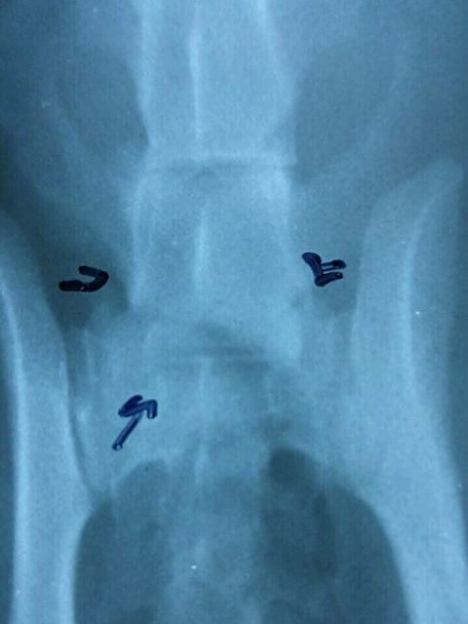

Unfortunately Ian is a lot sicker than we thought. Other than a hairline fracture of the lumbar spine and an air rifle pellet close to the lungs, he also has severe hemoplasma and feline herpes virus.